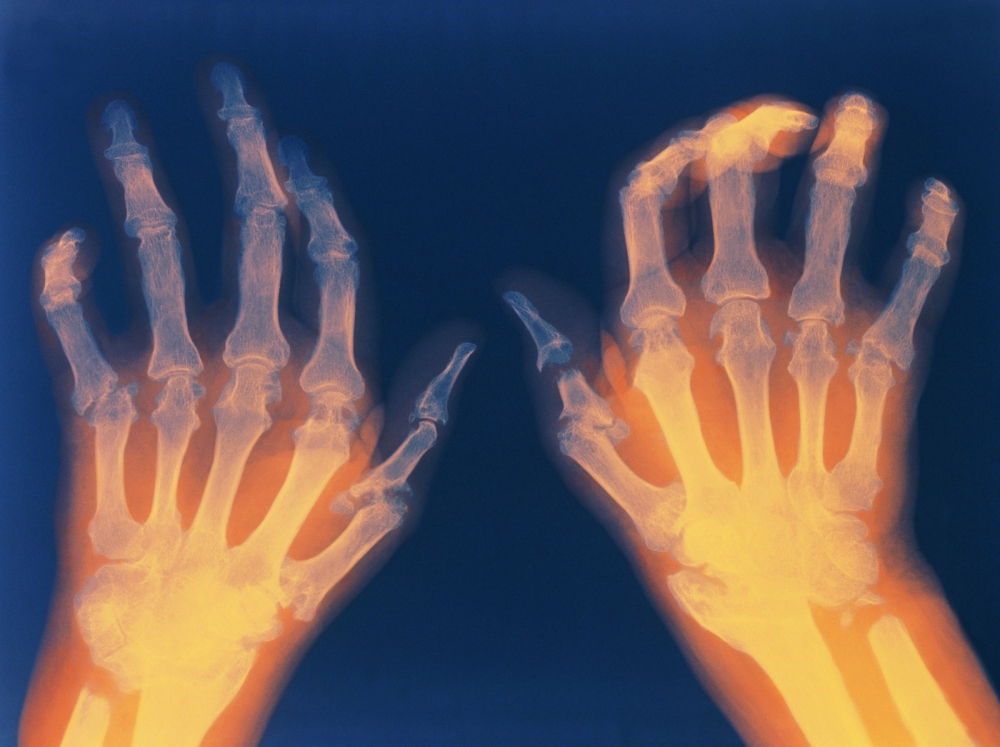

"Rheumatoid arthritis is a chronic inflammatory disorder that primarily affects the joints, but it can also impact other organs such as the lungs, heart, skin, nerves, muscles, blood vessels, and kidneys," Dr. Premkumar stated. "The condition causes pain and swelling in the joints, which is particularly evident in the fingers, toes, and spinal joints, leading to restricted movement."

He further explained that the disease affects the synovium, the lining of the joints, leading to inflammation and periarticular arthritis. This inflammation can result in significant pain and impaired joint mobility. When small joints in the hands are affected, it can interfere with daily activities such as eating, mixing food, and holding utensils, potentially leading to malnourishment.

Diagnosing rheumatoid arthritis involves a combination of clinical examinations and various tests, including the Rheumatoid Factor (RF), CCP antibody test, C-reactive protein (CRP), Erythrocyte Sedimentation Rate (ESR), Anti-Nuclear Antibody (ANA), Complete Blood Count (CBC), and X-rays. Factors such as age, sex (with a higher prevalence in women), family history, smoking, obesity, stress, and genetic susceptibility (which accounts for about 60%) also play a role in the disease's development.